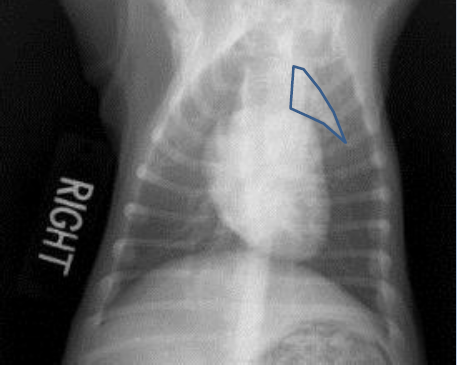

Feline

Mass on right side